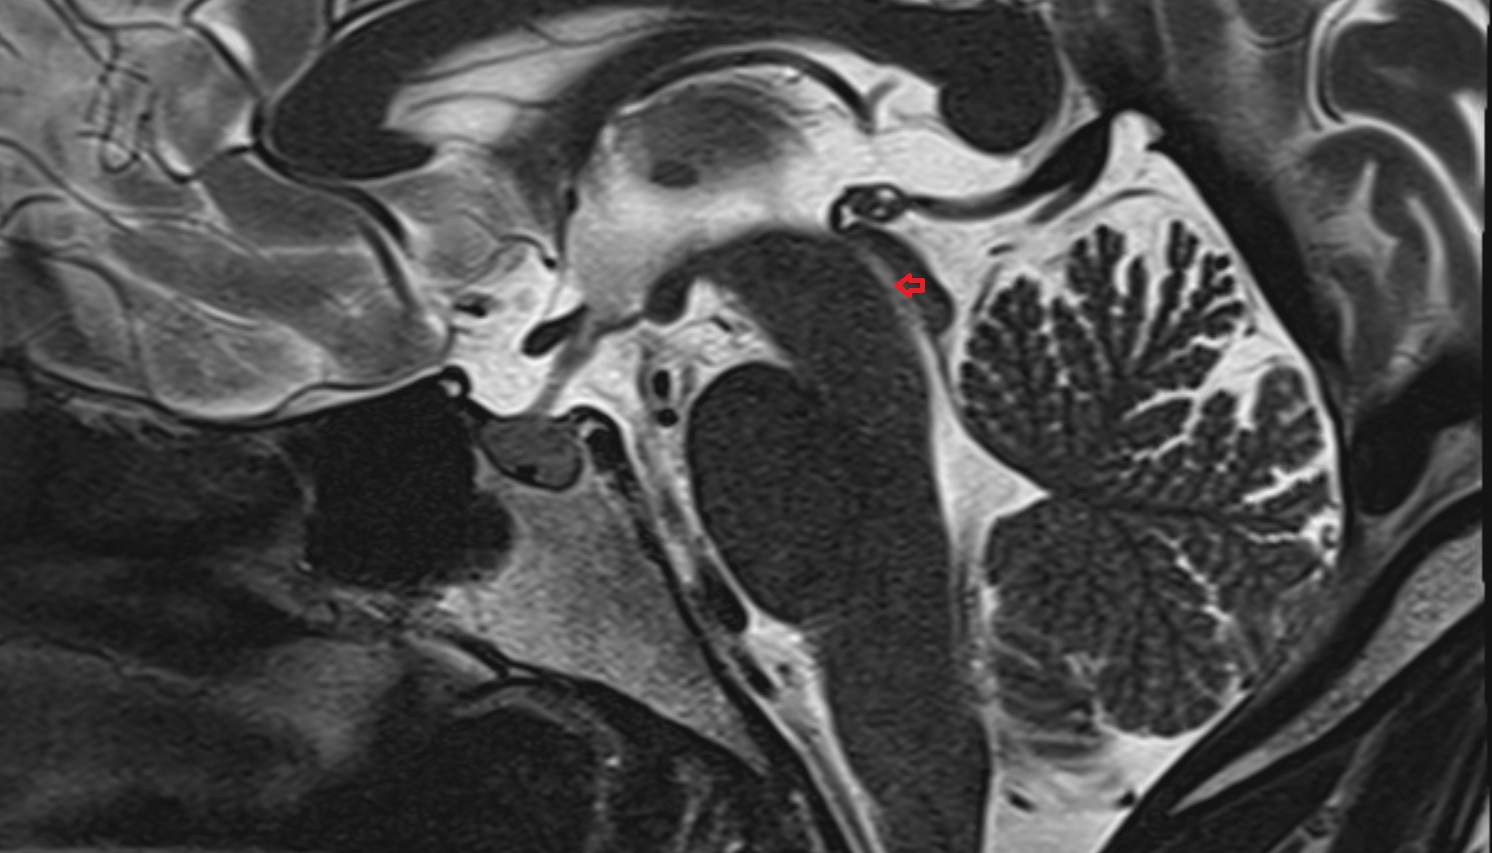

- Cerebellum

- Central lobule (II & III) of Cerebellum

- Culmen (IV, V) of Cerebellum

- Declive (VI) of Cerebellum

- Nodule of vermis (X)